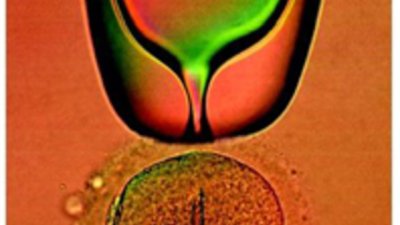

Новото в асистираните репродуктивни технологии